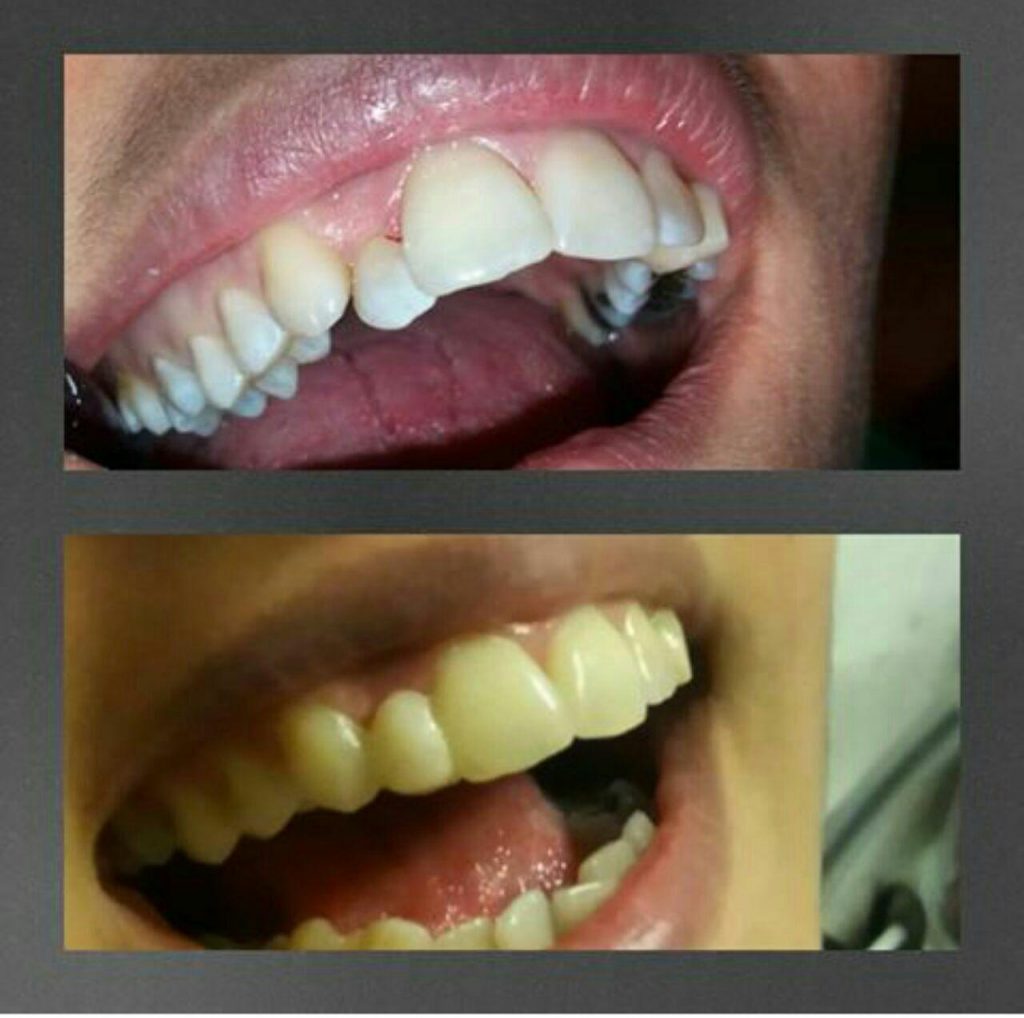

چگونه از دندان مصنوعی خود مراقبت کنم؟

اگر دندانهای مصنوعی روی زمین بیفتند، ممکن است بشکنند. همیشه پروتز خود را در یک کاسه آب و کاملا تمیز نگه دارید. برای تمیزکردن دندان مصنوعی، قانون کلی این است: هر روز آنها را مسواک بزنید و خیس کنید.

ابتدا دندانهای مصنوعی خود را مسواک بزنید تا تکههای غذا از بین برود. از یک پاککننده دندان مصنوعی غیر ساینده استفاده کنید، نه خمیردندان. مراقب باشید که خیلی محکم آنها را مالش ندهید زیرا ممکن است باعث ایجاد شیارهایی در سطح آنها شود.